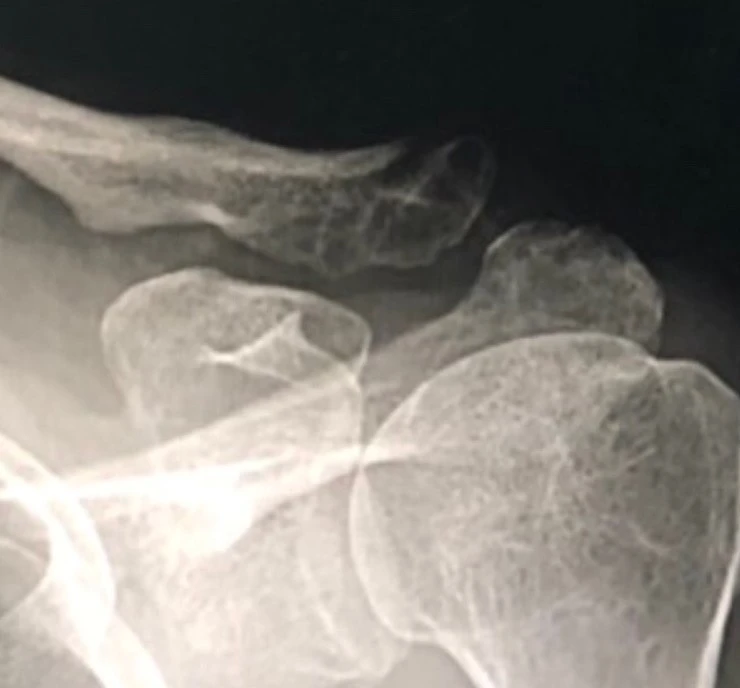

11주차 엑스레이

그리고 16주차 아침에 병원 진료에서 엑스레이를 확인했다. 의사는 이제 엑스레이 그만 찍어도 된다고 하시며, 팔을 들어보라시더니 도수치료는 좀 더 받아야겠다고 말했다. 내가 생각해도 지난 3주간 큰 진전이 없는 듯했다. 의사는 다음달에 보자는 말을 남겼지만 사실상 이젠 더 진료를 보지않아도 된다는 걸 나는 직감했다. 현재 상태에 나쁜 방향으로 이변이 없다면 말이다.